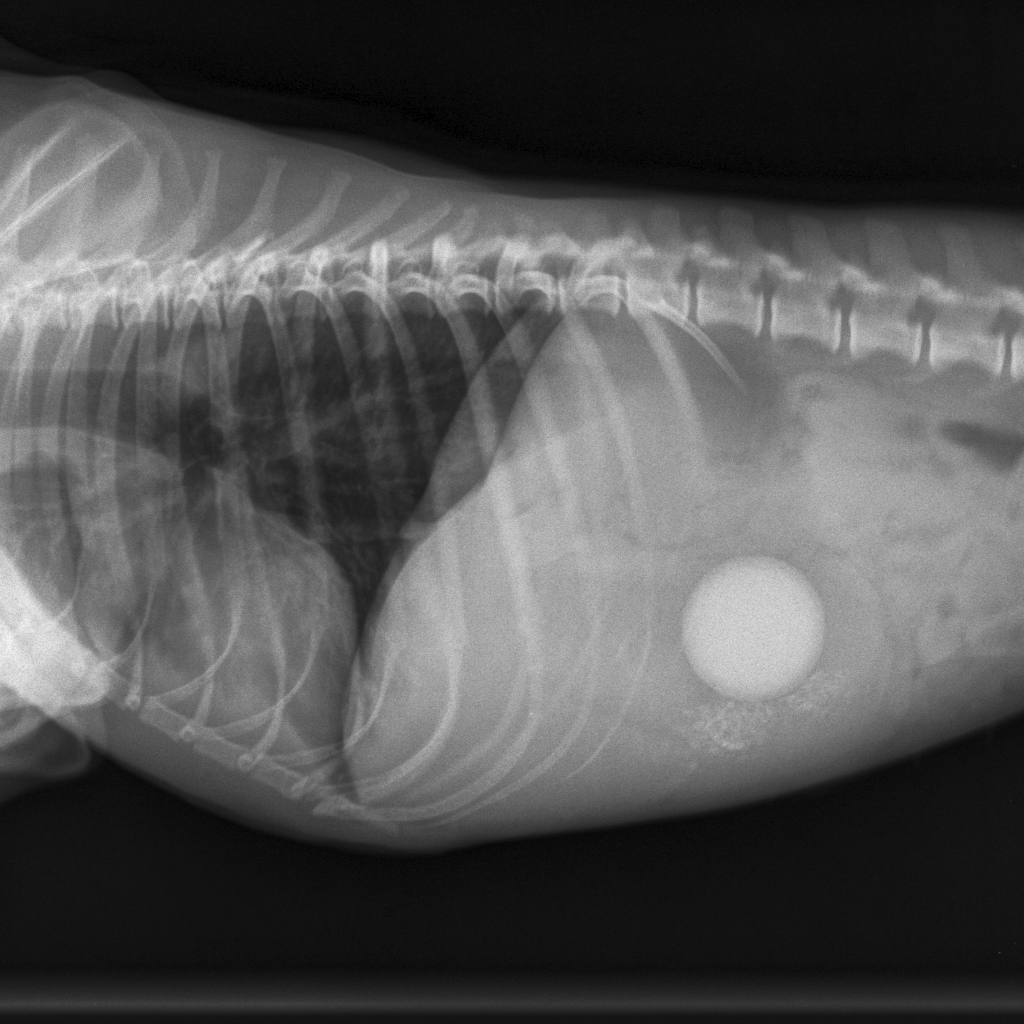

Bij het onderzoek op de praktijk blijkt Lady een erg pijnlijke buik te hebben en een hoge hartslag. Ze heeft wat verhoging en voelt zich alles behalve goed. Op de röntgenfoto is goed te zien wat lady in de weg zit.....de verloren stuiterbal is waarschijnlijk gevonden. We hebben middels een operatie de stuiterbal uit de maag verwijderd en Lady was vrijwel driect weer als nieuw! We zijn nu een dikke week verder en Lady doet alsof er nooit wat gebeurd is. Hopenlijk levert het ook een leermomentje op voor in de toekomst. Hieronder ziet u enkele foto's van Lady.

De röntgenfoto van de buik van Lady.

De stuiterbal is goed te zien.